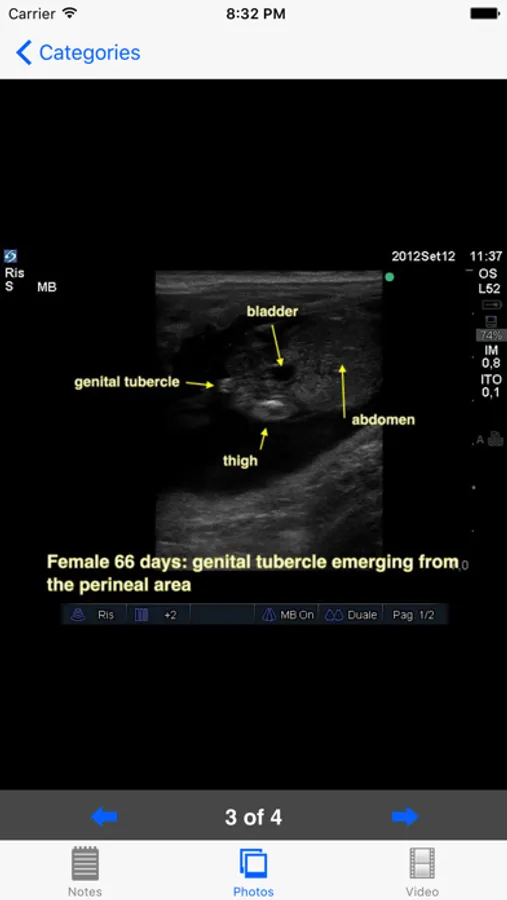

•Fetal sexing

Comprehensive notes are included for each condition with multiple still images. Fetal sexing is described and carefully illustrated in multiple planes for each stage of gestation. The still pictures demonstrate the classic appearance of each stage and are labeled where necessary. The video loops simulate the real life situation and allow the user to test their observational skills on moving images. This is an invaluable tool for continuing professional education of any veterinarian interested in stud work.